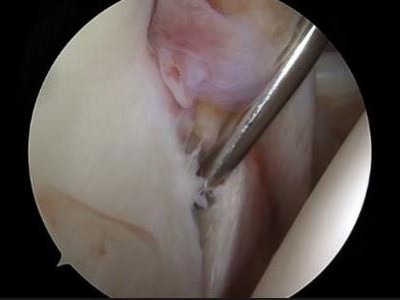

Rotatorenmanschettenruptur: konservative oder operative Therapie?

Die Behandlung von Rotatorenmanschettenrupturen erfordert therapeutisch komplexe Entscheidungen. Zentral sind die sorgfältige Patientenselektion und das rechtzeitige Erkennen des richtigen Zeitpunkts für eine Operation, um irreversible Schäden zu vermeiden.

Berliner Dom/© Photocreo Bednarek / Stock.adobe.com, Ärzteteam führt Hüftoperation durch/© ATRPhoto / stock.adobe.com (Symbolbild mit Fotomodell), Ein älteres Pärchen fährt Fahrrad/© Halfpoint / stock.adobe.com (Symbolbild mit Fotomodellen), Frau greift an ihre Ferse/© Satjawat / stock.adobe.com (Symbolbild mit Fotomodell), Distale Radiusfraktur/© Joel bubble ben / stock.adobe.com, Frau bei Knochenmineraldichte-Messung/© gelmold / stock.adobe.com (Symbolbild mit Fotomodell), Viele Ärzte versorgen einen Patienten/© Monkey Business / Stock.adobe.com (Symbolbild mit Fotomodellen), Röntgenbild Hüftprothese/© oceandigital / Fotolia, Transmurale Ruptur der Supraspinatussehne/© Wahal N et al. / all rights reserved Springer Medizin Verlag GmbH, Bluttransfusion im Rettungshubschrauber/© [M] Chalabala / Stock.adobe.com, Physiotherapeutin behandelt Fußbeschwerden/© aldomurillo / Getty Images / iStock (Symbolbild mit Fotomodellen), Narbe nach Kniegelenkersatz-Operation/© GalinaSt / stock.adobe.com (Symbolbild mit Fotomodell), DGOU Logo/© Deutsche Gesellschaft für Orthopädie und Unfallchirurgie, Berlin/© eyetronic / Stock.adobe.com, Hallux valgus/© Springer Medizin, Modell des Kniegelenks/© edwardolive / Stock.adobe.com (Symbolbild), Lumbale Spinalkanalstenose/© Birkenmaier C & Fuetsch M / all rights reserved Springer Medizin Verlag GmbH, Anteriore Schulterluxation im Röntgenbild/© Spagna G et al. / all rights reserved Springer Medizin Verlag GmbH, Chirurginnen und Chirurgen im OP/© Tobilander / stock.adobe.com (Symbolbild mit Fotomodellen), Schulterarthroskopie/© Issara / stock.adobe.com (Symbolbild mit Fotomodellen), Elektronenmikroskopisches Bild eines Biofilms an einer Titanoberfläche (Vergr. 1500:1)/© Holinka J, Windhager R doi.org/10.1007/s00132-016-3247-8 unter CC-BY 4.0, Primäre Hüftgelenkendoprothetik nach Azetabulumfraktur/© Hofmann GO et al. / Springer Medizin Verlag 2008, Osteosynthese einer distalen Radiusfraktur /© Mathias Ernert, Ärztin erklärt einem Patienten das Hüftgelenk/© Daisy Daisy / Stock.adobe.com (Symbolbild mit Fotomodell), Periprothetische Femurfraktur/© Springer Medizin, Vorderes Kreuzband/© Springer Verlag GmbH, MRT-Sequenz vom Knie/© Springer Medizin, Schweres Thoraxtrauma/© Christoph Nau · Birte Weber · Ingo Marzi / all rights reserved Springer Medizin Verlag GmbH, Ruptur der Rotatorenmanschette/© Springer Medizin, Wirbelkörper/© CreVis2 / Getty Images / iStock, Hallux valgus/© masanyanka / stock.adobe.com, Rotatorenmanschette/© Springer Verlag GmbH, Röntgenbild eines künstlichen Hüftgelenks/© Nicolas Larento / Fotolia, Minimalinvasive AC-Gelenk-Operation/© Springer Medizin, Rettungsassistenten liefern Notfallpatientin auf einer Trage in ein Krankenhaus ein/© Stephan Jansen / dpa / picture alliance, Idiopathische Skoliose/© Springer Medizin Verlag GmbH, Bandscheibenvorfall der LWS schematisch /© psdesign1 / Fotolia, Frau fasst sich an die Wade/© KSR / Fotolia , Liposarkom/© Davorin Wagner / Chirurgie im Bild, Narbe nach Kniegelenkersatz/© Miriam Dörr / Fotolia (Symbolbild mit Fotomodell), Weiße Tabletten im Blister/© bogo-service / Fotolia